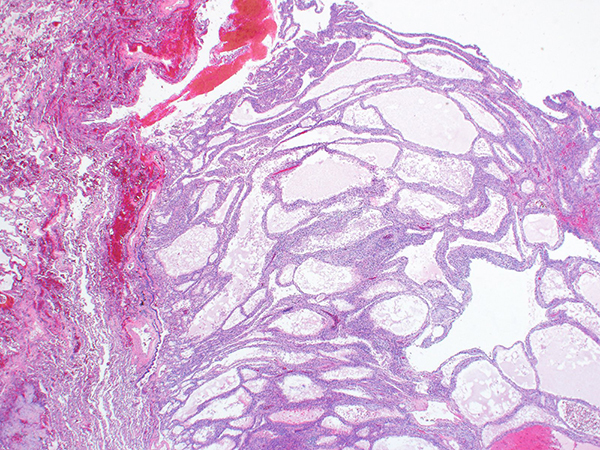

The imaging characteristics are of those of a benign tumor, showing a well-circumscribed and homogeneous mass with no to low level PET positivity. Transbronchial biopsy, bronchial washing, and fine needle aspiration are mostly non-diagnostic as the findings are non-specific, but can point to a benign process. Grossly, the tumors are well-demarcated and unencapsulated and have a multicystic cut surface. Histologically, the cystic spaces are empty or filled with eosinophilic granular material and scattered foamy macrophages (Figures 2-6). The larger cysts usually are concentrated in the middle of the tumor (Figure 2). The cystic spaces are lined by bland, flattened or hobnailed type II pneumocytes (Figures 3 and 4). The stroma may be myxoid and can contain variable numbers of inflammatory cells admixed with bland fibroblasts or fibroblast-like cells (Figures 5 and 6).